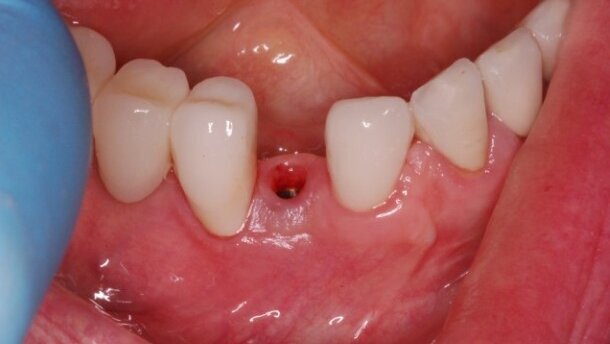

Po upływie 22 miesięcy od wykonania finalnej rekonstrukcji protetycznej doszło do poprzecznego pęknięcia korzenia zęba #12. Podjęto decyzję o natychmiastowej implantacji w tym miejscu. Wybrano poddziąsłowy protokół gojenia. Pacjentka nie wyraziła zgody na wykonanie przeszczepu łącznotkankowego celem zwiększenia objętości dziąsła związanego w okolicy przyszyjkowej implantu.

Odsłonięcia struktur kostnych dokonano poprzez wykonanie nacięcia poprowadzonego podniebiennie od szczytu wyrostka bez wykonywania horyzontalnych cięć odbarczających. Wprowadzony został implant Astra 3,5 mm (AstraTech AB, Szwecja), a powstała od strony przedsionkowej dehiscencja i fenestracja została pokryta materiałem BioOss (Geistlich Pharma, Szwajcaria) oraz membraną resorbowalną BioGide. Rana została zaszyta szwami pojedynczymi.

Zaplanowano 16-tygodniowy okres gojenia. Na czas gojenia wykonano odbudowę tymczasową, wykorzystując koronę z utraconego filaru.

Ryciny pokazują sytuację po odsłonięciu implantu i 2-tygodniowym okresie gojenia z wykorzystaniem śruby gojącej. Na implancie wykonano koronę tymczasową z kompozytu, co umożliwiło jej łatwą modyfikację w gabinecie. Stwierdzono prawie 2 mm recesję dziąsła oraz brak brodawek dziąsłowych przy zębach sąsiednich.